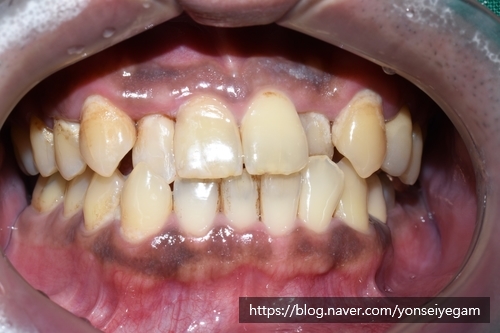

심한 위쪽 앞니 4개 심한 충치 치료만 진행한 후의 사진입니다.

앞에서 보이던 충치(화살표부분)도 레진 치료로 자연스럽게 레진 충치치료가 된 상태입니다.

앞니 외의 다른 치아들도 치료가 필요한 상태입니다.